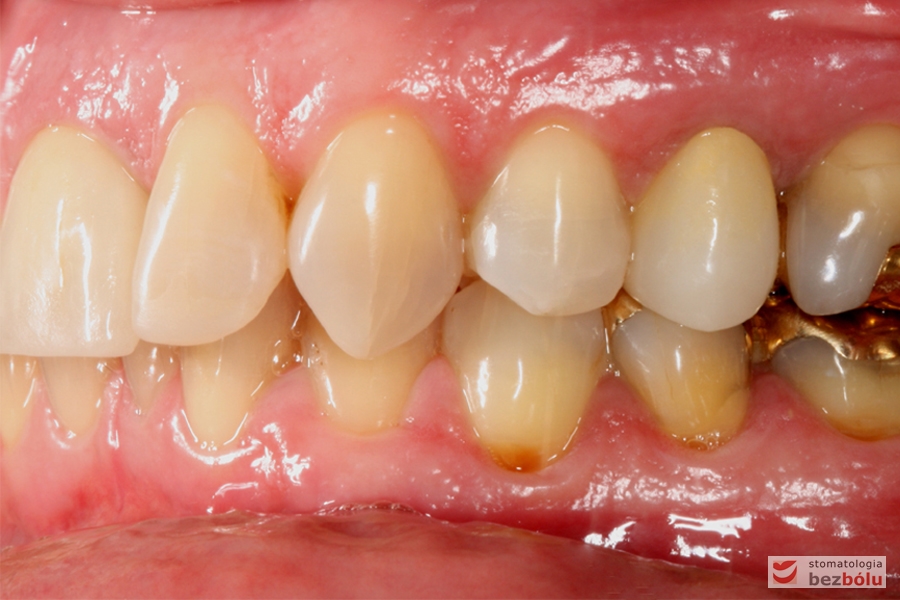

Do naszej placówki zgłosiła się starannie planująca swoje działania Europejka, mieszkająca na stałe w Kotlinie Jeleniogórskiej. Jej oczekiwania dotyczyły bardzo metodycznie zaplanowanego planu leczenia. Celem jaki postawiła przed naszym zespołem lekarzy było wyeliminowanie wszystkich wątpliwych i nierokujących wypełnień, a także poprawa estetyki w zakresie lewego siekacza centralnego w szczęce. Został rozpisany blisko dwuletni plan wymiany zużytych i nieszczelnych wypełnień amalgamatowych i kompozytowych. Zaplanowano również przygotowanie endodontyczne wybranych zębów w szczęce i żuchwie, a także zaopatrzenie w inlay’e porcelanowe i korony ceramiczne wykonane w systemie e-max.